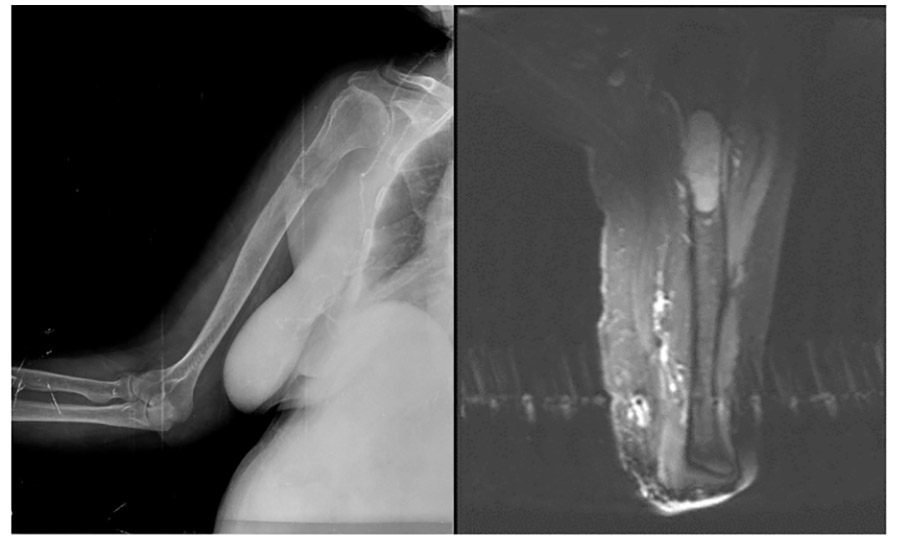

CASE 4: Risk of fracture in the right arm (humerus) due to metastasis of kidney cancer (RCC - Renal cell carcinoma).

Before the surgery: The X-ray shows damage to the upper end of the humerus, and the MRI shows tumor tissue completely filling that area.